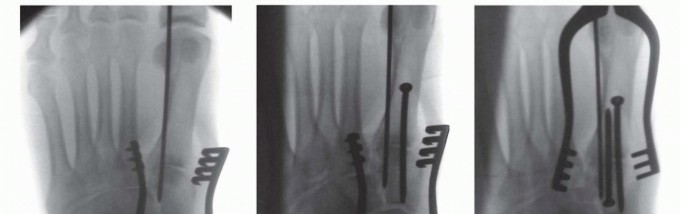

The provisional reduction is held with a 2.0-mm Kirschner wire and confirmed under fluoroscopy (

TECH FIG 3A

).

TECH FIG 3 • Reduction and stabilization of first tarsometatarsal joint. A. Provisional reduction. B. Distal to proximal screw. C. Proximal to distal screw. D. Long bicortical trajectory of screws for enhanced stability. Definitive stabilization is then obtained at the first tarsometatarsal joint with 3.5-mm solid cortical position screws (

TECH FIG 3B-D

The first screw is placed from distal to proximal, starting at the dorsal crest and distal to the metaphyseal-diaphyseal junction, and is angled toward the plantar-proximal cortex of the medial cuneiform; this screw is generally 45 to 50 mm long.

A second screw is placed from proximal to distal starting at the edge of the naviculocuneiform joint and similarly angled to exit at the plantar cortex distal to the metaphyseal-diaphyseal junction. This screw typically measures 40 to 45 mm.

In a primary arthrodesis, these screws are placed in lag fashion.

For larger patients, 4.0-mm cortical screws may be used for further stability.

TECH FIG 4 • Reduction and stabilization of Lisfranc joint. A. Pointed reduction forceps. B. Supplemental Kirschner wire. C. Screw fixation. Trajectory of screw mirrors the normal path of ligamentous structures. Intercuneiform joint was previously reduced and stabilized as initial step.Lisfranc Joint A pointed reduction forceps is then placed from the medial cuneiform to the lateral border of the second metatarsal to anatomically reduce the so-called Lisfranc joint; care is taken to ensure accurate dorsal-plantar alignment of the second tarsometatarsal joint.

The reduction is confirmed under fluoroscopy, and a 2.0-mm Kirschner wire that mirrors the intended path of the screw is placed to provide further rotational control (

TECH FIG 4A,B

There is typically a distinct cortical “shelf” on the medial cuneiform that provides an excellent buttress for screw purchase.

A 3.5-mm cortical screw is placed through a stab incision overlying this cortical shelf medially, angling toward the proximal metaphysis of the second metatarsal; for a primary arthrodesis, this screw is placed in lag fashion (

TECH FIG 4C

Other Joints

If the intercuneiform joint is involved, it is first reduced and stabilized before stabilizing the Lisfranc joint (

TECH FIG 5A

). Alternatively, this joint may also be reduced and stabilized before stabilizing the first tarsometatarsal joint.

A 3.5-mm cortical screw is again used, coursing parallel to the plane of the naviculocuneiform joint. It is placed in lag fashion for a primary arthrodesis.

Care is taken not to violate the articulation between the middle and lateral cuneiform.

The second tarsometatarsal joint is then provisionally reduced and provisionally stabilized with a 1.6-mm Kirschner wire.

Definitive fixation is obtained with a countersunk 2.7-mm cortical screw from distal to proximal; it is placed in lag fashion for a primary arthrodesis (

TECH FIG 5B

--- TECH FIG 5 • A. Reduction and stabilization of intercuneiform joint. B. Reduction and stabilization of second tarsometatarsal joint. C. Reduction and stabilization of third tarsometatarsal joint.

TECH FIG 5 •

(continued)

D. Comminuted second metatarsal and second and third tarsometatarsal joints. E,F. Second and third metatarsals and segmental fourth metatarsal in a different patient. G. Kirschner wire fixation of fourth and fifth tarsometatarsal joints.

H.

Reduction and stabilization of cuboid through separate proximal-lateral incision.

I.

Fluoroscopic image.

The third tarsometatarsal joint is reduced and stabilized in identical fashion (

TECH FIG 5C

For a metatarsal base fracture or fracture-dislocation pattern precluding transarticular fixation, bridge plate fixation may be required.

We prefer a low-profile (2.0 or 2.4 mm) reconstruction plate and 2.4-mm cortical screws (

TECH FIG 5D-F

The fourth and fifth tarsometatarsal joints are then reduced and definitively stabilized with 1.6-mm Kirschner wires.

Because the intermetatarsal ligaments between the third, fourth, and fifth metatarsals are often preserved, these joints may anatomically reduce indirectly, thereby allowing percutaneous stabilization.

The Kirschner wires are contoured and buried beneath the skin layer through separate stab incisions, which facilitates removal at 6 weeks postoperatively, either in the office under local anesthesia or in the operating room under sedation (

TECH FIG 5G

For a cuboid fracture, the cuboid is reduced and definitively stabilized to ensure restoration of lateral column length before stabilizing the fourth and fifth tarsometatarsal joints; by definition, this is then an open reduction (

TECH FIG 5H

Final fluoroscopic images are obtained, confirming articular reduction and implant placement (

TECH FIG 5I